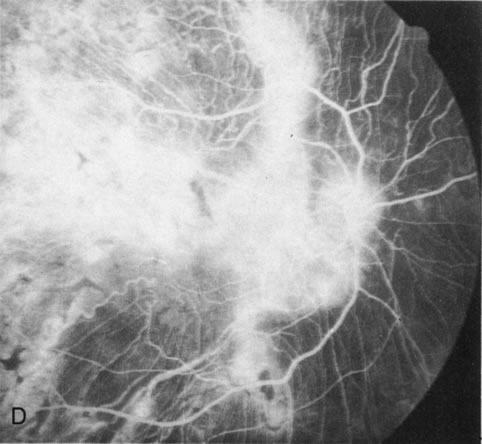

Of more clinical importance is the role of FA in the diagnosis and treatment of cystoid macular edema (CME) (Fig. 1C and D). Stereoscopic FA indicates that the leakage, which may be diffuse or have the typical petaloid stellate appearance of CME, can come from the perifoveal retinal capillaries, from the choroid through the RPE, or from a combination of both sources.4 With the recent suggestion that CME in RP may be successfully treated with acetazolamide,5, 6 FA is thus important to document the diagnosis of CME, establish the origin(s) of leakage, and follow patients during and after therapy.